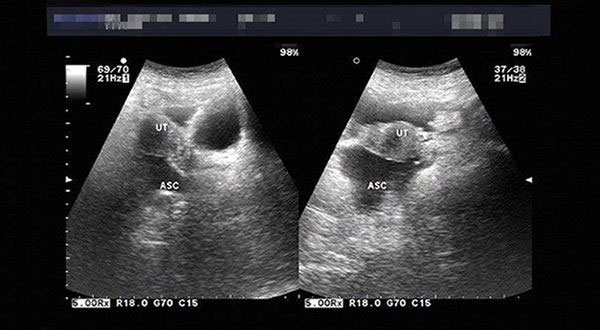

B超检查下的盆腔积液